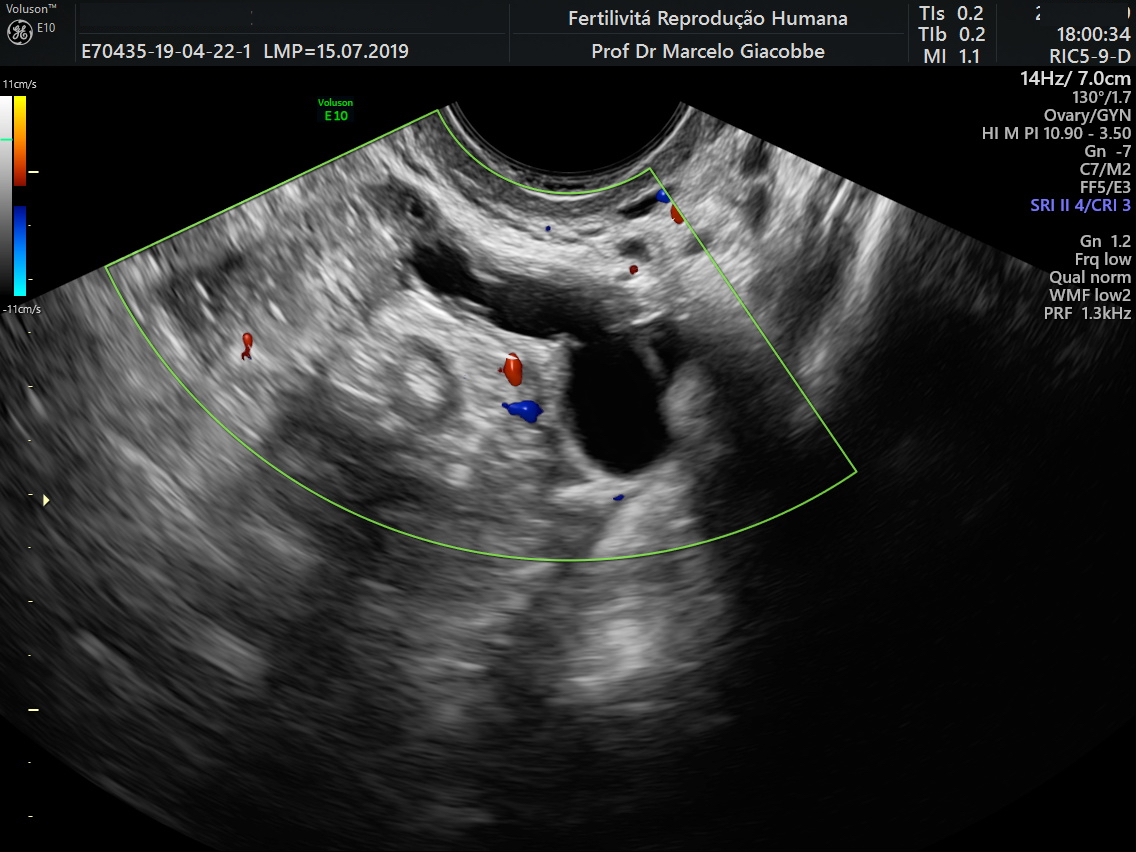

Imagem de ultrassom mostrando hidrossalpinge